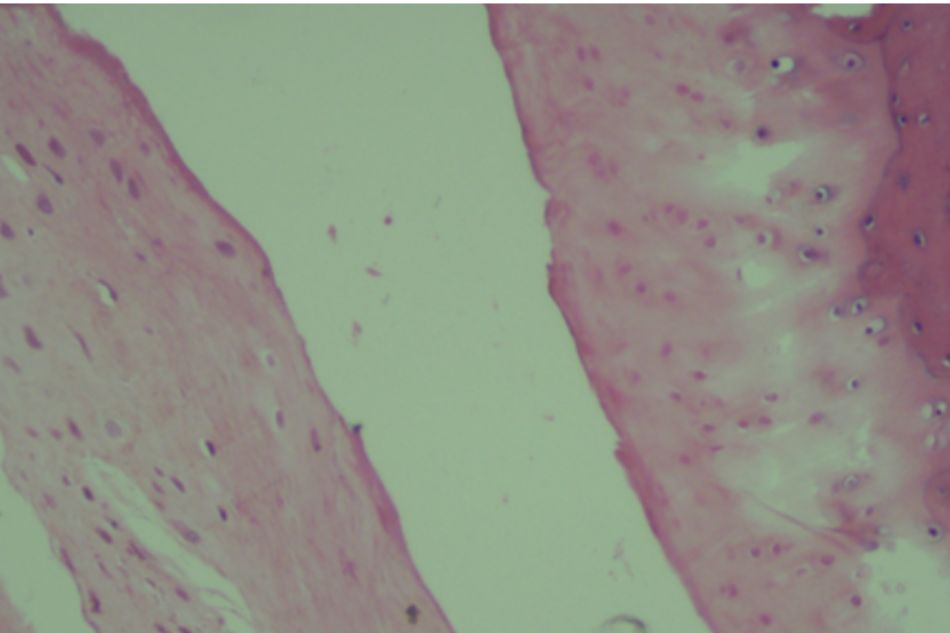

Figure 2.3. Knee joint sample in Group II (rat no.11)

Moderate subchondral bone and cartilage damage

Figure 2.4. Knee joint sample in Group II (rat no.12)